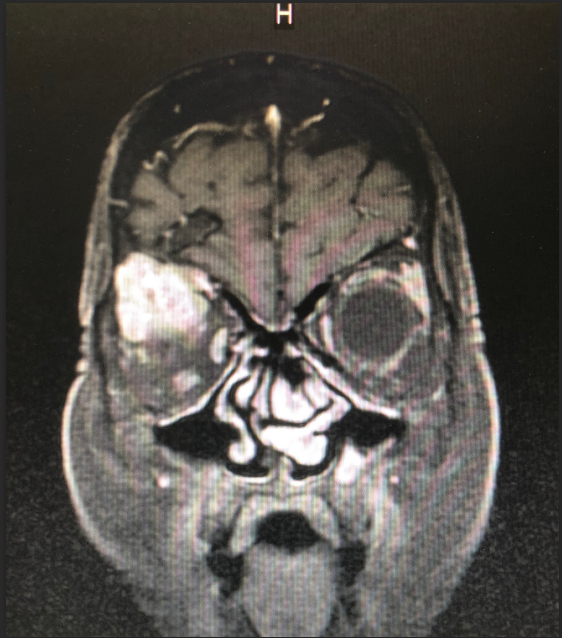

患者王女士,79岁,女性,2周前出现右眼疼痛,眼球突出,随后眼痛逐步加重,右眼视力急剧下降。在当地医院被诊断为眼眶内肿瘤,需手术治疗。但因患者眼眶肿瘤突破眼眶,向颅内生长,手术难度大。患者先后辗转多家医院眼科均无功而返。患者右眼疼痛难忍,最终选择到探花av 寻求最后的帮助。

探花av 神经外科团队接诊后对患者进行了全面检查,诊断为右眼眶肿瘤。因患者肿瘤向颅内生长,颅底及眼眶骨质已完全破坏,传统的手术方式不仅创伤大,更可能因为颅底结构无法完全重建导致患者脑脊液漏,引起颅内感染。神经外科联合眼科进行了手术方式的讨论,根据术中可能出现的各种情况其制定了详细的治疗方案,认真完善术前准备后,于2018年12月24日成功为其开展“完整切除颅内外沟通瘤并颅底眼眶重建修复手术”,手术过程非常顺利,术后患者无视神经损伤,视力较术前明显改善。目前患者已康复出院。